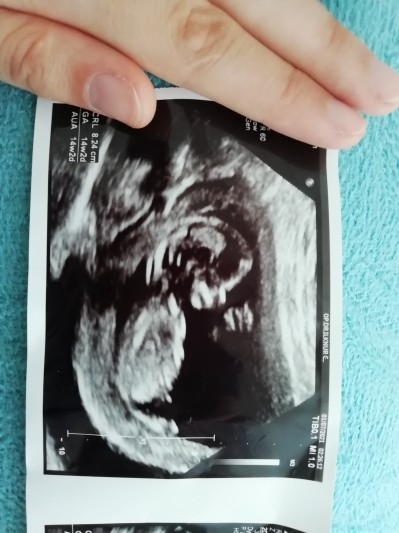

Kızlar böyle sorular gördüğümde yazanlar oluyordu biz nerden bilelim doktor bişi demediyse diye lütfen o kişiler yazmasin:) ben paylaşmak için yazıyorum az çok yorum yapanlar oluyor sizce acaba cinsiyeti ne :)

Gebelik haftası 12+2

Kız his ettim :)

Kız gibi sanki bir çıkıntı aradım ama bulamadım :) sağlıkla gelsin inşallah ♥️

Henüz çok yeni hislerime dayanarak söylüyorum ben kız hissettim :) sağlıklıca gelsin kuzucuk önce sağlığı yerinde olsun :)

Hic yorum yapmadım boyle soruya ilk defa yapiyorum bana erkek gibi geldi saglikli sihhatli olsun da

Kız gibi görünüyor

Erkek sanırsam bak resim atıyorum bu da benim oğlumun cinsiyetini öğrendiğimiz foto